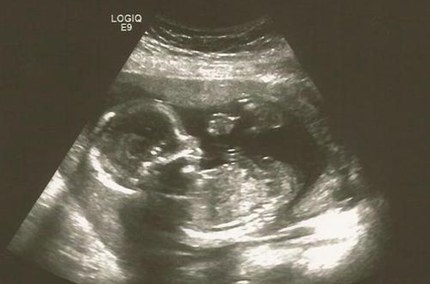

NT单子上会有宝宝的图片,我们在上面的图片可以看到具有性征的一些身体特点,男孩的特征点与身体呈45度角,还多一些,而女孩儿的特征点几乎和躯体平行。还有就是如果是男宝宝,屁股位置会微微上翘,后背脊柱成圆弧状,因为要留空间发育前列腺,相反,女宝宝后背脊柱就相对就平一些。

NT指的是出现在胎儿颈部的一个透明液体,它的作用主要是用于胎儿早期唐氏综合征的风险评估。NT并不会一直存在与胎儿的颈部,它只是在某一个特定时间断短暂出现一段时间而已,NT大约在胎儿11周左右会出现,胎儿发育到14周时,NT逐渐会被胎儿体内的淋巴系统所吸收,变成另一种东西,即颈部褶皱,简称FN。